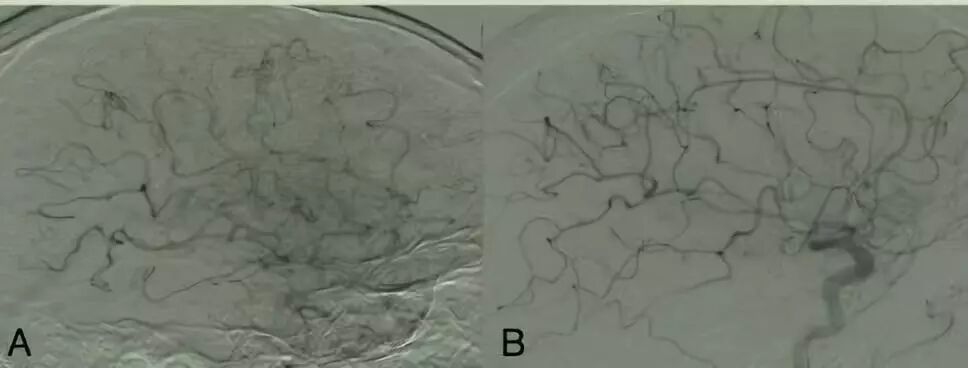

图2

A血流分级eTICI 2b50 (50–66%)

B血流分级eTICI 2b67(67–89%)